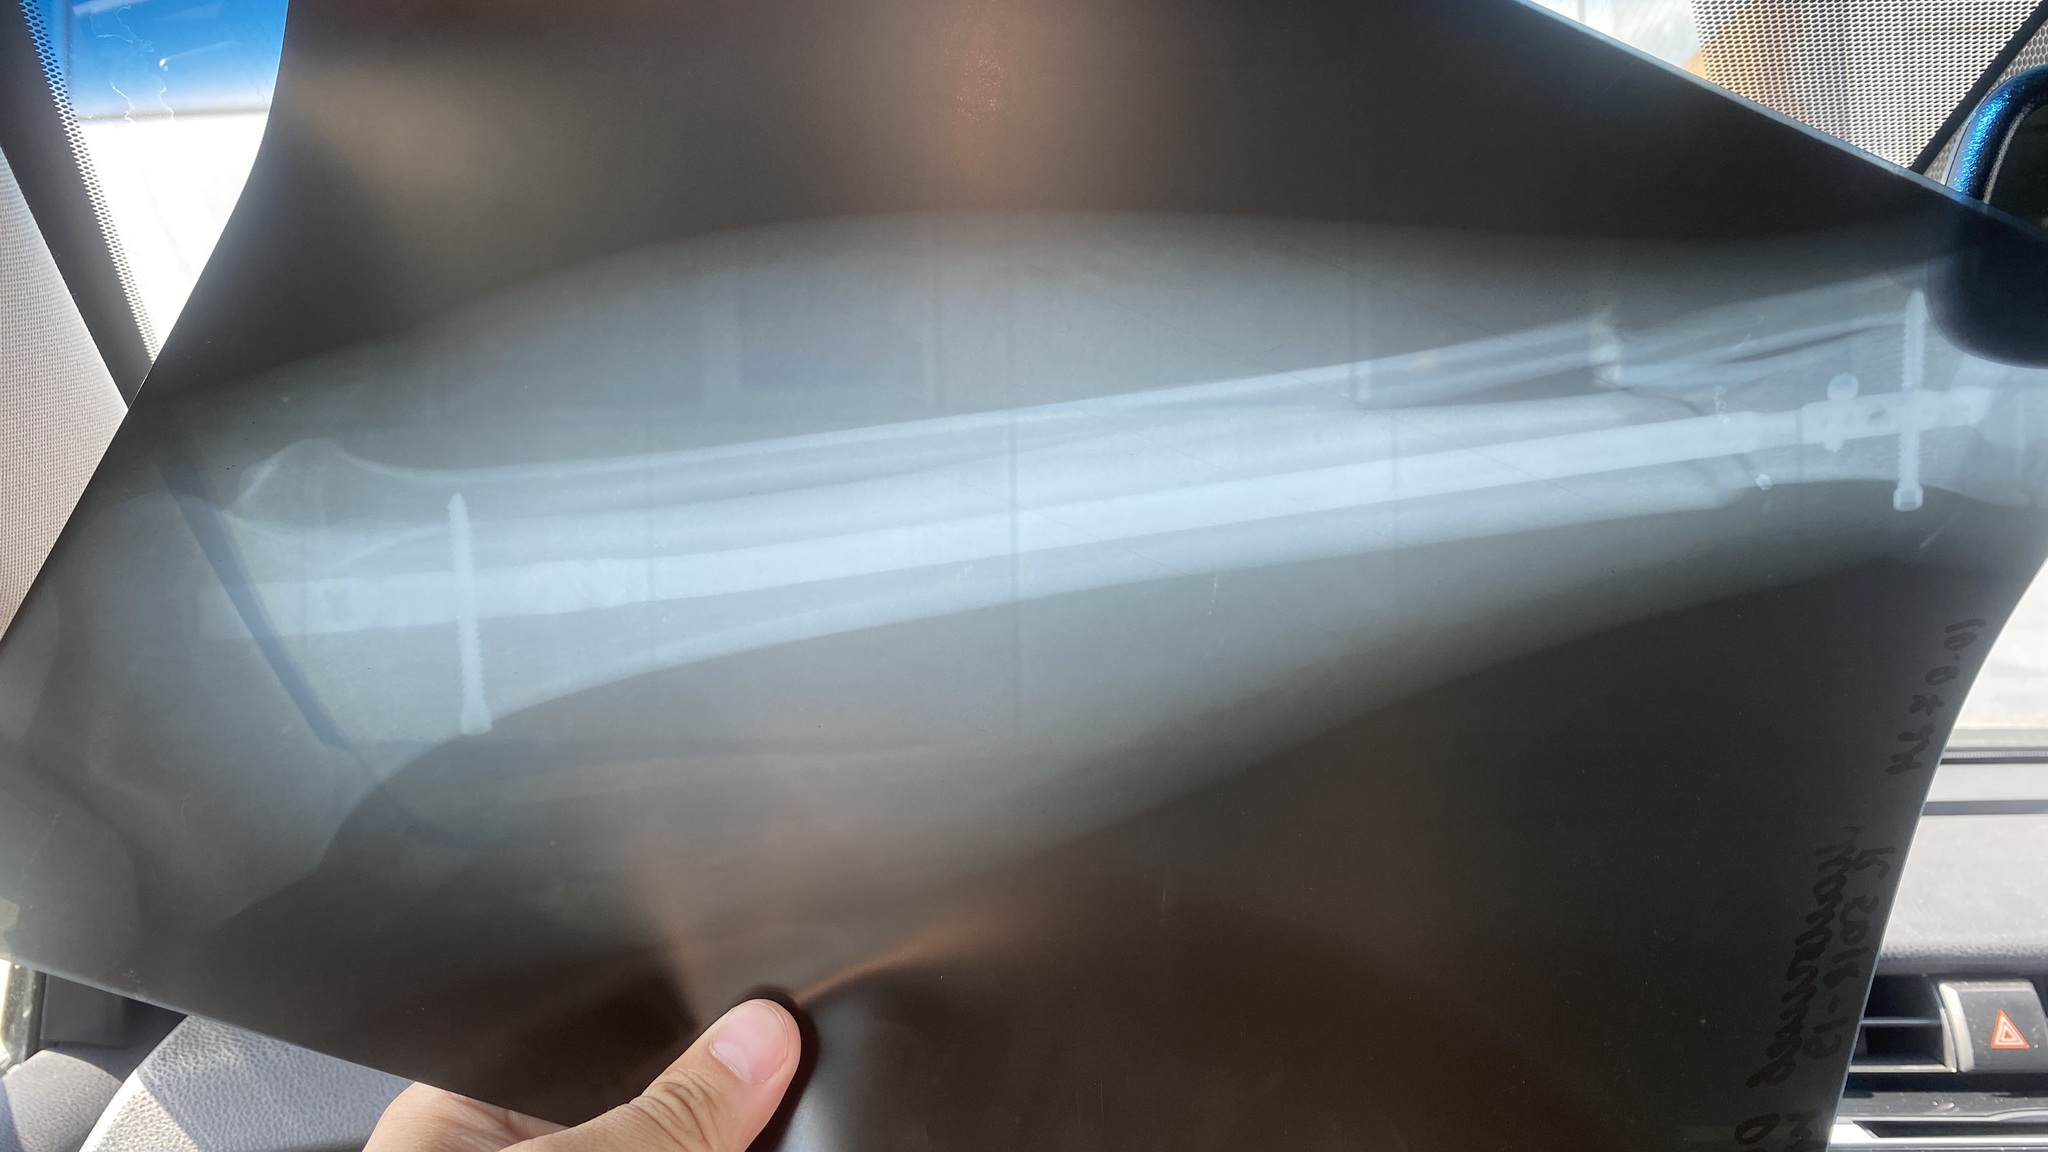

Вот одна из систем для интрамедуллярного остеосинтеза. Конструкция сверху - она снаружи, а сам стержень внутри бедренной кости

Длинная под углом - это отвертка, которая вкручивает винты в стержень. На самом стержне есть несколько отверстий для винтов, которыми он фиксируется. Чтобы вставить стержень внутрь кости, нужно сделать канал внутри нее.

Наборов много. Например, INTERTАN, SАNАTMETАL (для интрамедуллярного остеосинтеза плеча) и т.д. И все они в общем похожи, но имеют много-много нюансов.

Нашлась картинка набора Gаmmа. Тут не все инструменты показаны. И здесь, возможно, набор не для ИОСа бедра, а для ИОСа плеча. У этого производителя есть наборы для плеча и бедра. И часть инструментов в этих наборах одинаковая